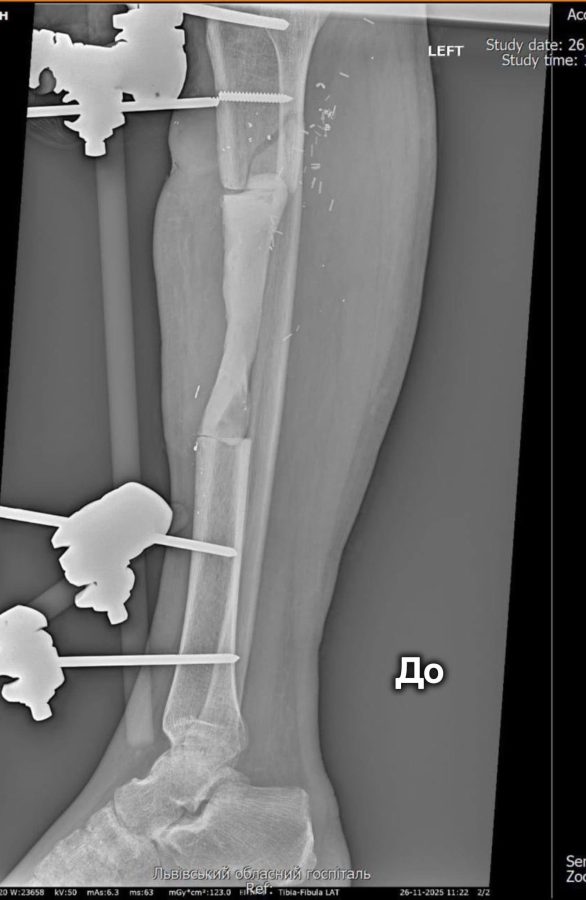

Пацієнтом став військовослужбовець із критичним дефектом кістки завдовжки 12,5 сантиметра. У подібних випадках стандартні методи лікування часто не дають результатів, тож медики вирішили застосувати техніку Маскулет. Вона передбачає два етапи: спочатку формується спеціальна «індукована мембрана» — своєрідна камера для кістки, а згодом її заповнюють кістковою тканиною та стабілізують уламки.

У госпіталі зазначають, що методику Маскулет часто називають «операцією останньої надії», адже вона дає шанс на відновлення у випадках важких вогнепальних поранень і значних втрат кісткової тканини. Цей метод дозволяє уникнути тривалого використання апаратів зовнішньої фіксації та скорочує шлях пацієнта до повноцінного відновлення.